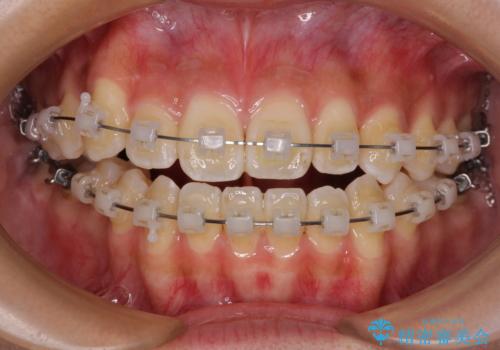

- クリアブラケット

- 1年6ヶ月

急速拡大装置で上顎骨を十分に拡大できたことで、非抜歯で八重歯を歯列に納めることができました。

患者様はもちろん、我々もここまで綺麗に仕上げられるとは想像もできず、お互いに大変満足な治療となりました。